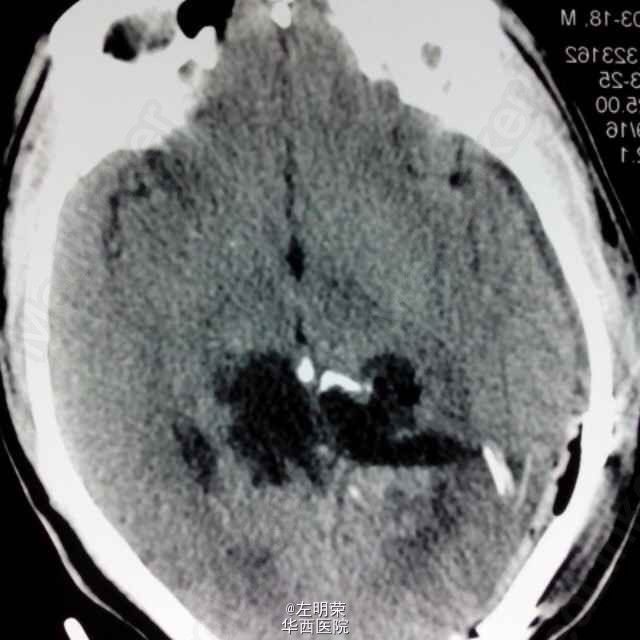

中年男性患者,“反复头痛一年”入院。查体未见明显异常;头部MRI示:松果体区占位,梗阻性脑积水。术中见病变位于右侧脑室三角区,病变范围广泛,侵及丘脑,脑干背侧,松果体区,呈白色珍珠状,质脆,切除过程中出血少,有白色坚韧包膜,予以全切,患者术后恢复良好;病理结果:松果体区表皮样囊肿。